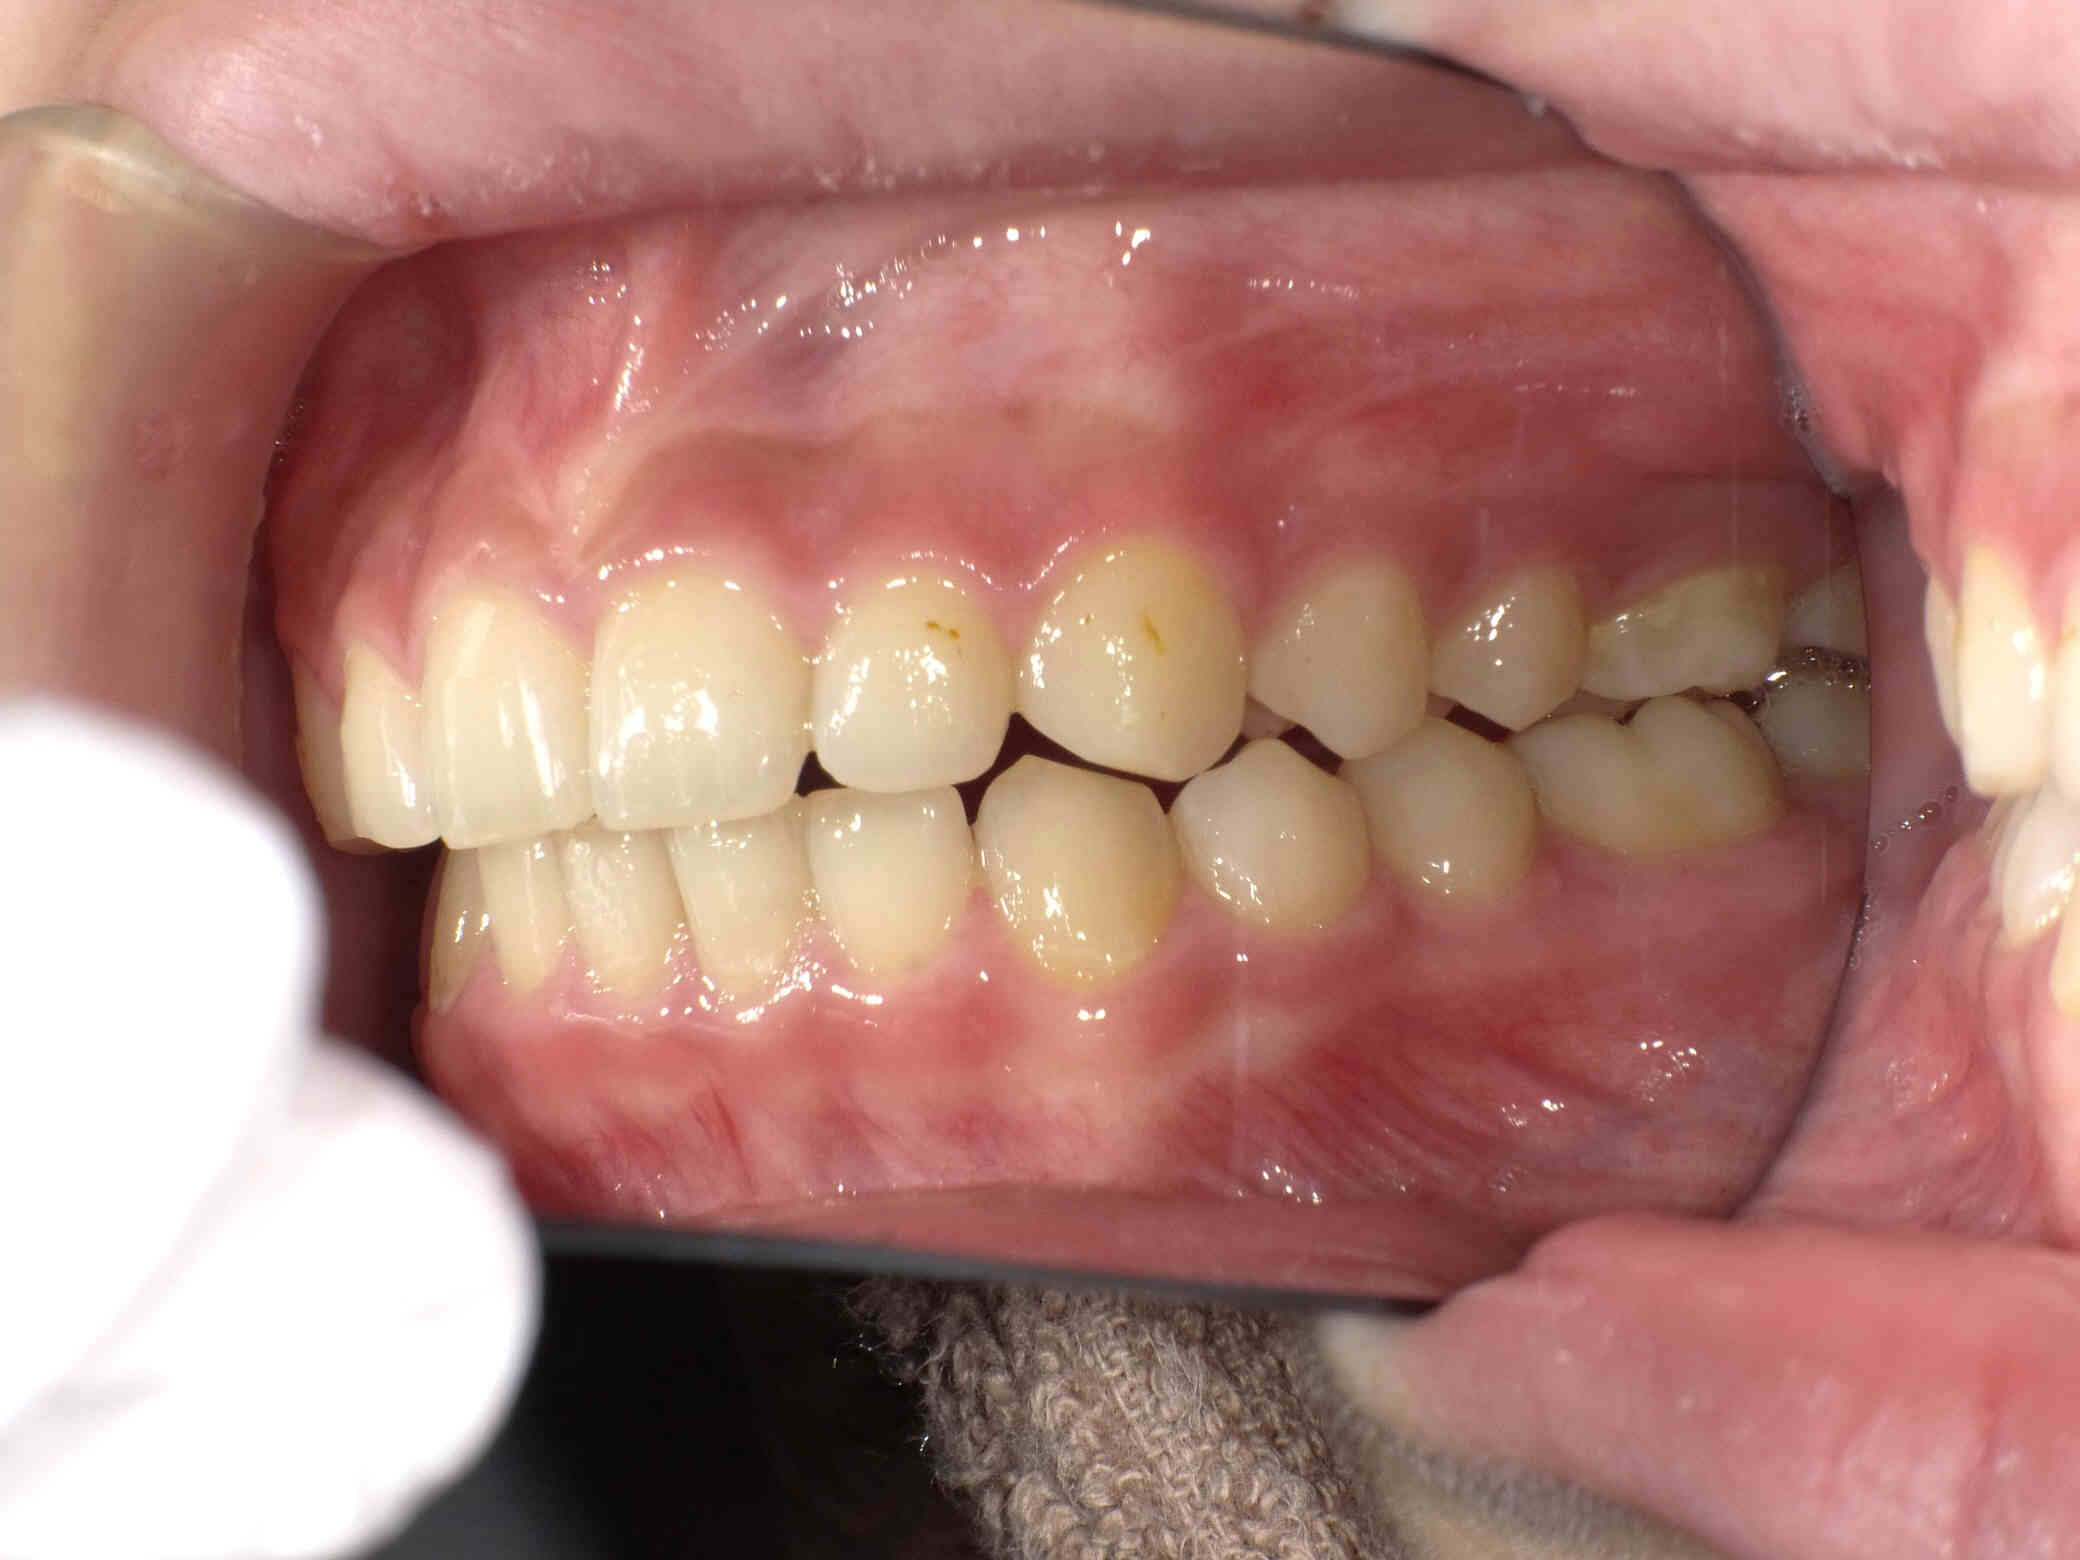

やや出っ歯傾向で、噛み合わせが深く

歯並びがデコボコな鋏上咬合(はさみじょうこうごう)という状況でした。

上下の歯がすれ違っている状態で、一部の歯に過度の負担がかかってしまいます。

今回はご希望のワイヤー矯正で治療を行い、スタートから1年半で美しい歯並びに改善しました。